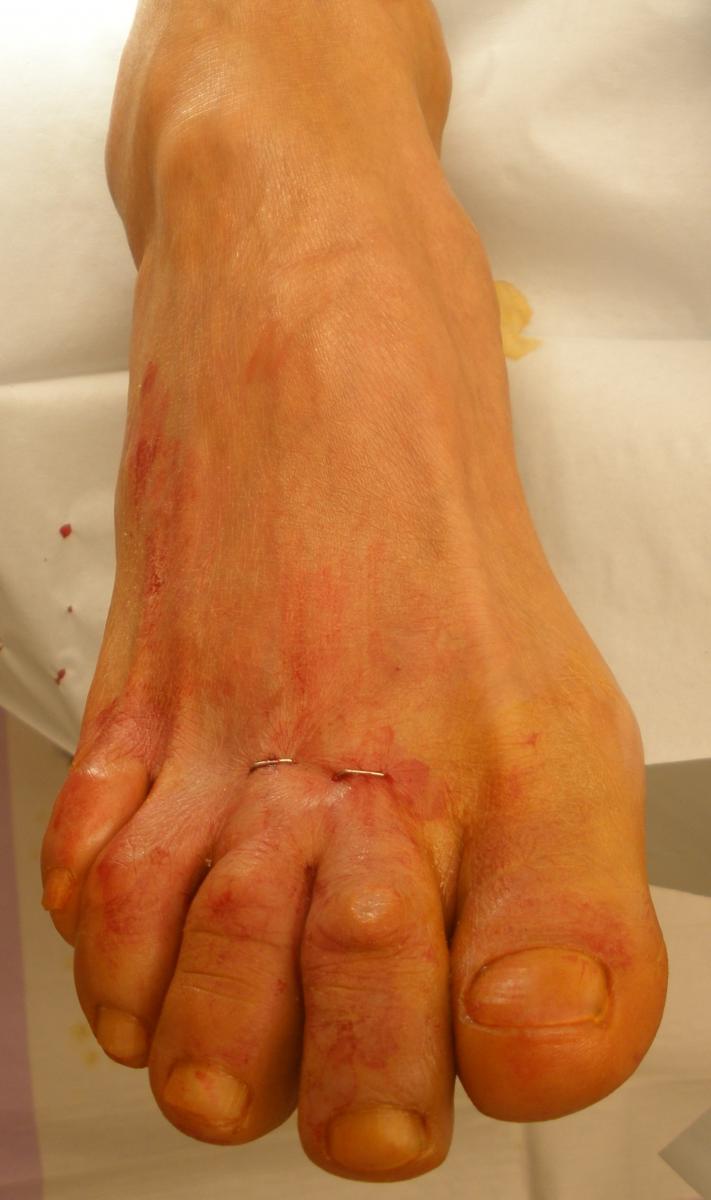

For a recurrent distal ulcer in the lesser toe in a patient with flexible hammertoe, perform a percutaneous extensor and flexor tenotomy to straighten the toe and eliminate pressure on the distal end of the digit.

One can perform this with the patient having a local anesthetic. Generally, I perform both a flexor and extensor tenotomy to avoid excessive dorsiflexion at the metatarsophalangeal joint (MPJ) if the flexor tenotomy occurs in isolation.

Utilize a 64 beaver blade for this procedure. Make the initial stab incision dorsal to the MPJ in a longitudinal fashion. Then deepen the blade to the level of the joint and rotate the blade medially and laterally, cutting the extensor tendon and joint capsule at that level. Plantarflex the toe at the MPJ to spread the tendon ends apart.

Then direct attention to the plantar aspect of the proximal interphalangeal joint of the toe (located at the toe sulcus). Make a linear incision with the 64 blade, deepening it to the level of the joint. Rotate the blade medially and laterally, cutting the flexor tendon and joint capsule at this level. Dorsiflex the toe to spread the cut ends of the flexor tendon apart. If adequate correction has not yet occurred, make an additional stab incision plantar to the distal interphalangeal joint of the digit and perform the identical procedure there. If the patient only has a mallet toe, the surgeon may only need to perform a single procedure plantar to the distal interphalangeal joint.

Following adequate release, close the skin with a single skin staple at each stab incision.3 Dress the surgical site with betadine-soaked gauze for splintage around the toes generally for two to three weeks. During this time, the patient remains partially weightbearing on the heel in a surgical shoe. Remove the skin staples and the patient returns to normal shoe gear. Inform patients preoperatively that they will not be able to grasp with the operated toes after surgery.4